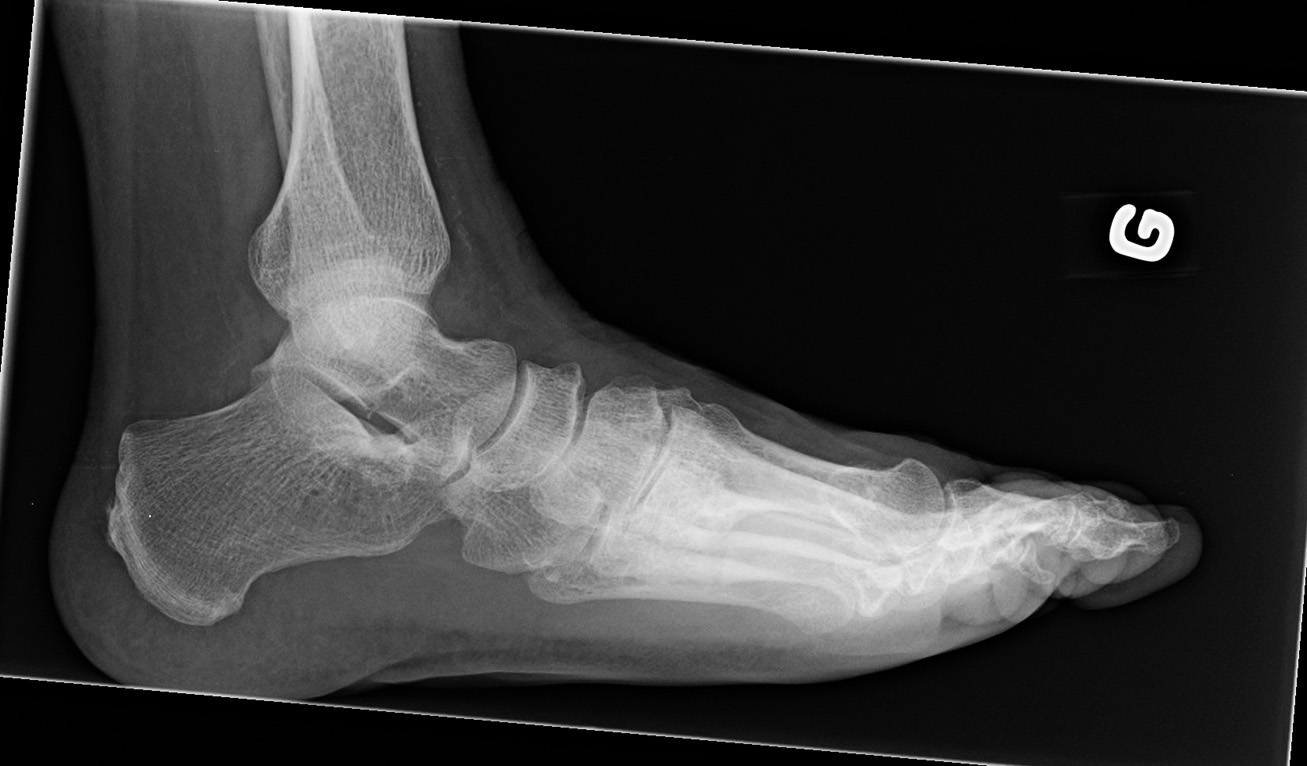

Lateral

• Anteroposterior

• Lateral

• Oblique

• Standing view of the feet